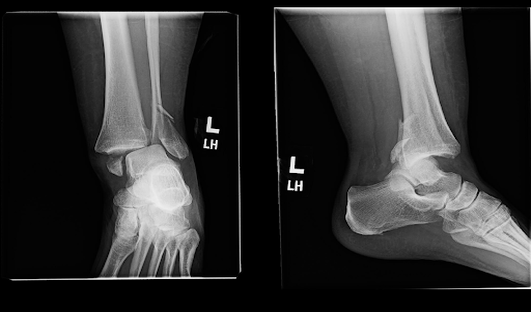

Le diagnostic repose sur une radiographie standard en 3 incidences :

Face, face en rotation interne de 20° et profil.

La radiographie retrouve la fracture et permet d’établir le diagnostic. Un scanner peut être demandé pour préciser le trait de fracture et orienter la décision chirurgicale.